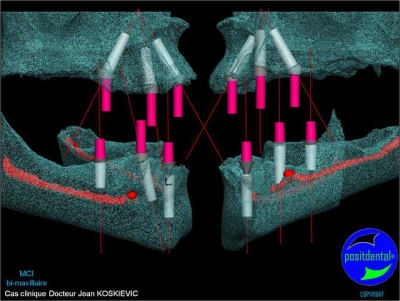

Je viens de recevoir les empreintes pour réaliser un Positscan en prévision d'une MCI bi-maxillaire. "chouette" un peu de métal pour corser l'histoire.

et la projet 10 implants maxillaire sup

5+5 ou 10+10

10 en haut

donc ce sera minimum 8 en fonction du scan